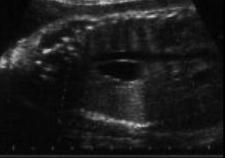

Image echographique prenatale d'une duplication

kystique au portion1/3 moyen de oesophage ( coupe

longitudinale ) |